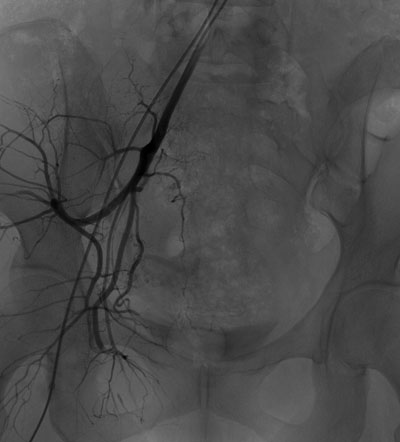

与家属充分沟通并签署知情同意书后,介入科肖红主任、谢元明主治医师、李芳琼护士长立即展开术前准备工作,通知李婷媛技师从家中赶来医院做好机器准备。手术于6月14日23:30开始,行股动脉插管,在DSA引导下迅速找到出血的子宫动脉,立即进行封堵治疗,于6月15日01:30成功完成双侧子宫动脉栓塞术,术后阴道出血明显减少,患者血压稳定,为患者行下一步宫腔镜手术减少术中出血保驾护航。

介入止血前后对照